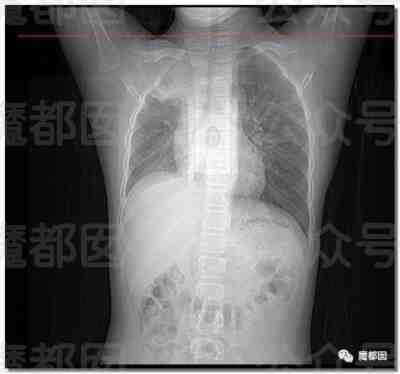

我们都晓得,正常情况下肺部是由肺泡组成的,肺泡里边是充满了空气的,进行CT或者是X线检查的时候,射线穿过肺泡的时候,影像的表现应该是黑色的区域,但是当肺泡里边出现炎症和感染,有渗出液和炎性细胞的时候,肺泡就被这些渗出液或者炎性细胞填充,这样射线就穿不透,在影像学上的表现就出现了白色的区域,这个白色区域反映出来的是渗出物的影像学的表现。

随着这些渗出液的吸收、炎症的消退,白肺的表现也会逐渐消退,也就是说肺部的影像学表现就会回到正常的黑色的区域。并不是只要肺部出现了炎症就都叫白肺,比较严重的肺炎的表现才会出现白肺,一般来讲肺部的炎症比较重,渗出比较多的时候,就是白色的影像区域面积达到了70%到80%的时候,才在临床上把它称为白肺。